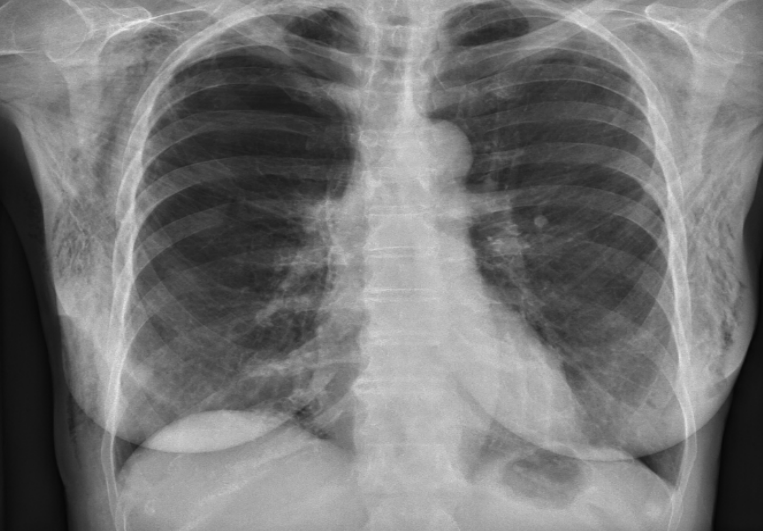

cardiomegaly

AP chest X ray and yet heart is still grossly enlarged